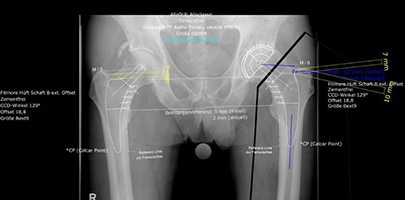

Präoperative Planung der Hüftprothese

HÜFT-TEP DER PATIENTIN

Deutliche Coxarthrose links

Coxarthrose links, Versorgung mit Kurzschaft-Prothese

Arthrose des linken Hüftgelenkes einer 52 jährigen Frisörin mit deutlicher Funktionseinschränkung und einer Gehstrecke unter 500m. Operative Behandlung mit einer Kurzschaftprothese mit gutem Ergebnis.